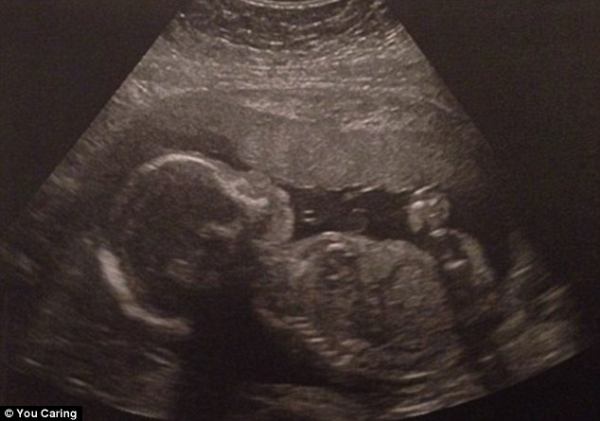

Anh Dylan Benson, 32 tuổi, cha của cậu bé, đã hết sức đau lòng khi chứng kiến người vợ yêu quí Robyn phải nằm liệt trên giường bệnh vì chứng chết não khi đang mang thai đứa con 22 tuần tuổi.

Các bác sĩ tại bệnh viện nơi Robyn điều trị cố gắng duy trì sự sống cho cô tới khi thai nhi được 34 tuần tuổi. Khi đó, họ có thể mổ để lấy đứa bé ra và hy vọng sống sót của em bé sẽ cao hơn. Tuy nhiên, người mẹ không chắc giữ được mạng sống.

Các bác sĩ tại bệnh viện nơi cô Robyn Benson điều trị phải đặt máy thở cho bệnh nhân liên tục trong nhiều tuần để thai nhi có thể tiếp tục phát triển. Nỗ lực của họ được đền đáp xứng đáng khi vào hôm 8-2, con trai của Robyn đã chào đời trước sự vui mừng của những người thân trong gia đình bà mẹ trẻ.